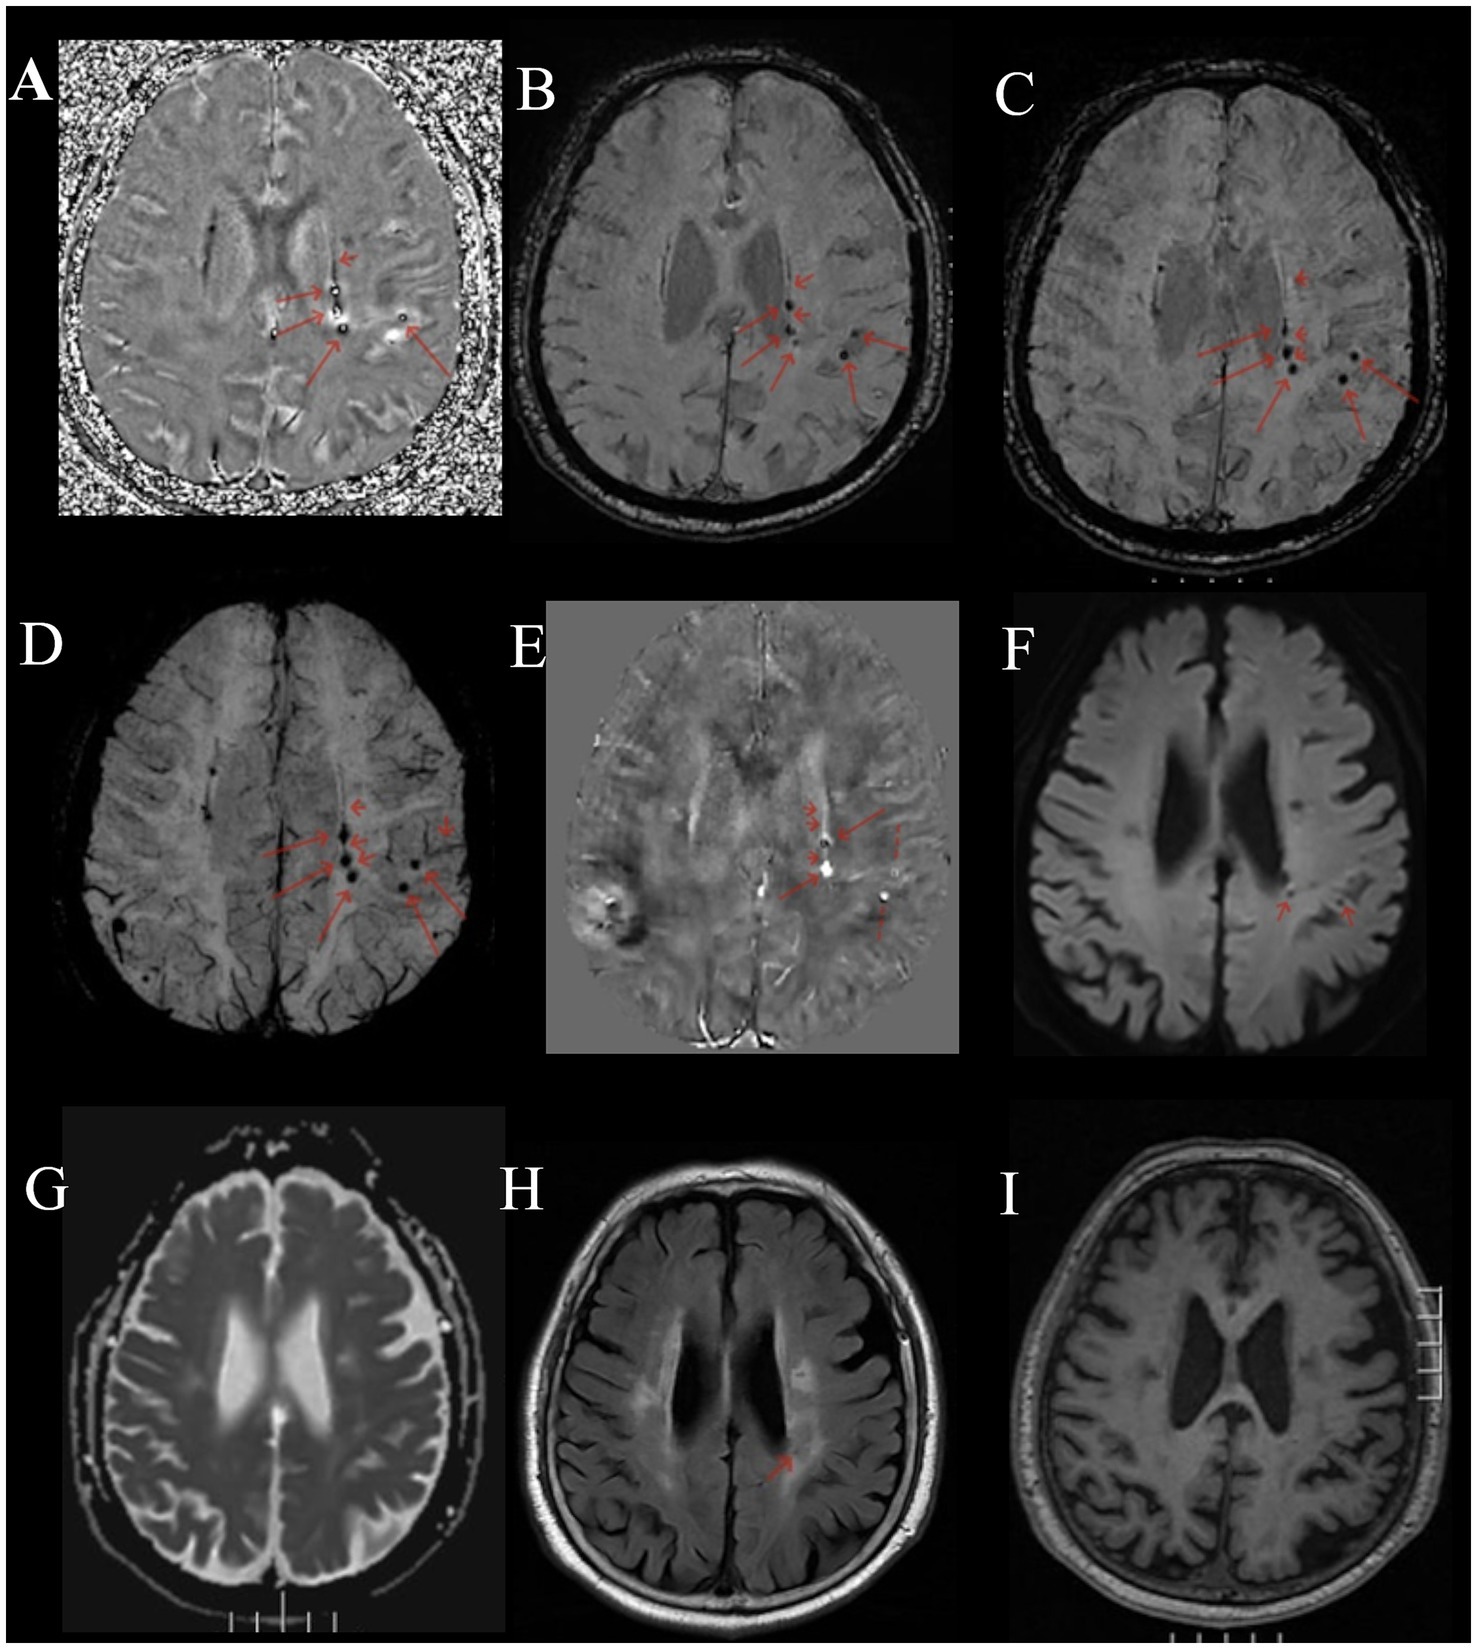

Compared to normal or other disease (see Supplementary material), on multi-echo SWI with long TE (22.5 ms), BCT lesions all presented as distinct small round hypointense signals on images, with punctate or strip-like slightly hyperintense signals at the center and a hypointense ring at the edge, forming a typical “single-ring target sign” (long red arrows in Figures 1A–D, 2A–G). Lesions had clear boundaries, and increased and thickened draining small veins were visible around the lesions (short red arrows in Figures 1A–D, 2A–G). QSM images showed round abnormal signals of lesions, with the central part being hyperintense due to the passage or penetration of central veins, a hypointense ring in the middle, and slightly hyperintense or hyperintense signals at the outermost edge, forming the most typical “double-ring target sign” (long red arrow in Figure 1E). The edges of some lesions showed a slightly hyperintense ring, and the inner side showed a hypointense ring, forming a typical “target sign” (dashed red arrow in Figure 1E). Meanwhile, increased and thickened small veins were observed around the lesions (short red arrows in Figures 1E, 2H). Some lesions only showed punctate hyperintense signals (solid long red arrow in Figure 1E). DWI, Flair, and T1WI images showed a few punctate hypointense signals (short red arrows in Figures 1F,H,I), and ADC showed punctate hyperintense signals (Figure 1G).

Figure 1

Male, 73 years old, with right limb motor impairment for 15 years and dizziness for 1 day. (A) Phase map. (B) Amplitude map. (C) SWI image. (D) MinIP image with TE of 22.5 ms. (E) QSM image. (F) DWI image. (G) ADC map. (H) FLAIR image. (I) T1WI image. (A–D) Round-like hypointense signals can be seen in the left periventricular region and the left parietal cortex, with hyperintense signals in the center, forming a typical “target sign” (long red arrow). The surrounding lesions show hypointense signals from the drainage of the left subependymal vein and parietal cortical vein (short red arrow). (E) QSM shows two round-like abnormal signals in the left periventricular region. The central part is the hyperintense central vein, the middle is hypointense, and the outermost edge is slightly hyperintense or hyperintense, forming the most typical “target sign” (long red arrow). The surrounding lesions have strip-like hyperintense subependymal vein drainage (short red arrow) passing through two BCTs (long red arrow). The left parietal cortex shows round-like lesions with hypointense in the center and hyperintense at the edge, forming a typical “target sign” (dashed long line). (F) DWI image, showing punctate hypointense signals in the left periventricular region and parietal cortex (short red arrow). (G) Shows slightly hyperintense signals. (H) Shows hypointense signals (short red arrow). (I) T1WI image, showing slightly hypointense signals.